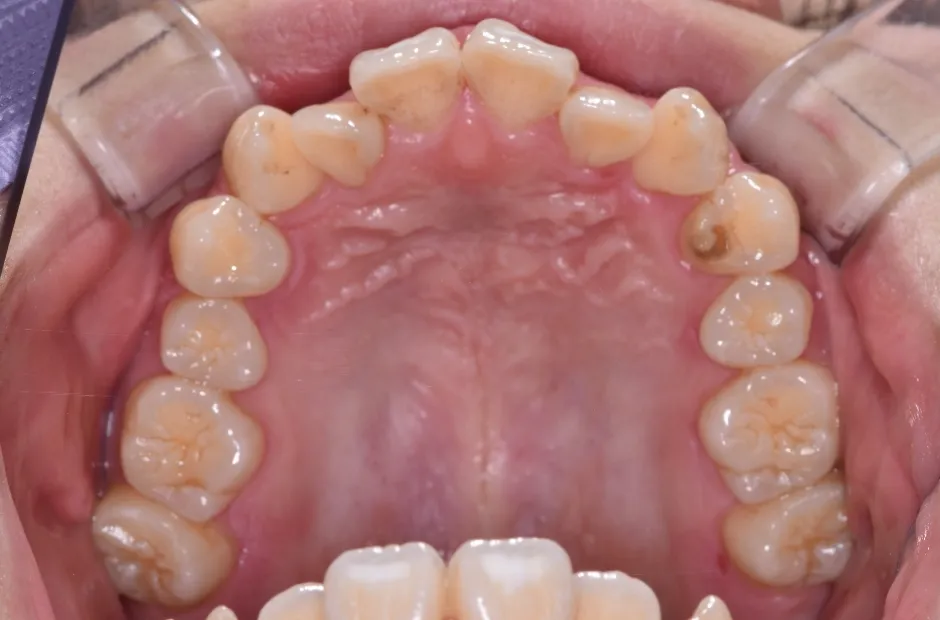

叢生

| 診断名・主訴 | 叢生 |

|---|---|

| 年齢・性別 | 43歳・女性 |

| 治療期間・回数 | 2年7か月 27回 |

| 治療に用いた主な装置 | 舌側矯正 |

| 抜歯部位 | 両顎4,4 |

| 治療費 | 100万円(税抜) |

| リスク・副作用 | 装置による違和感・疼痛・歯肉退縮・歯根吸収・虫歯のリスクなど |

治療前

治療中

治療後